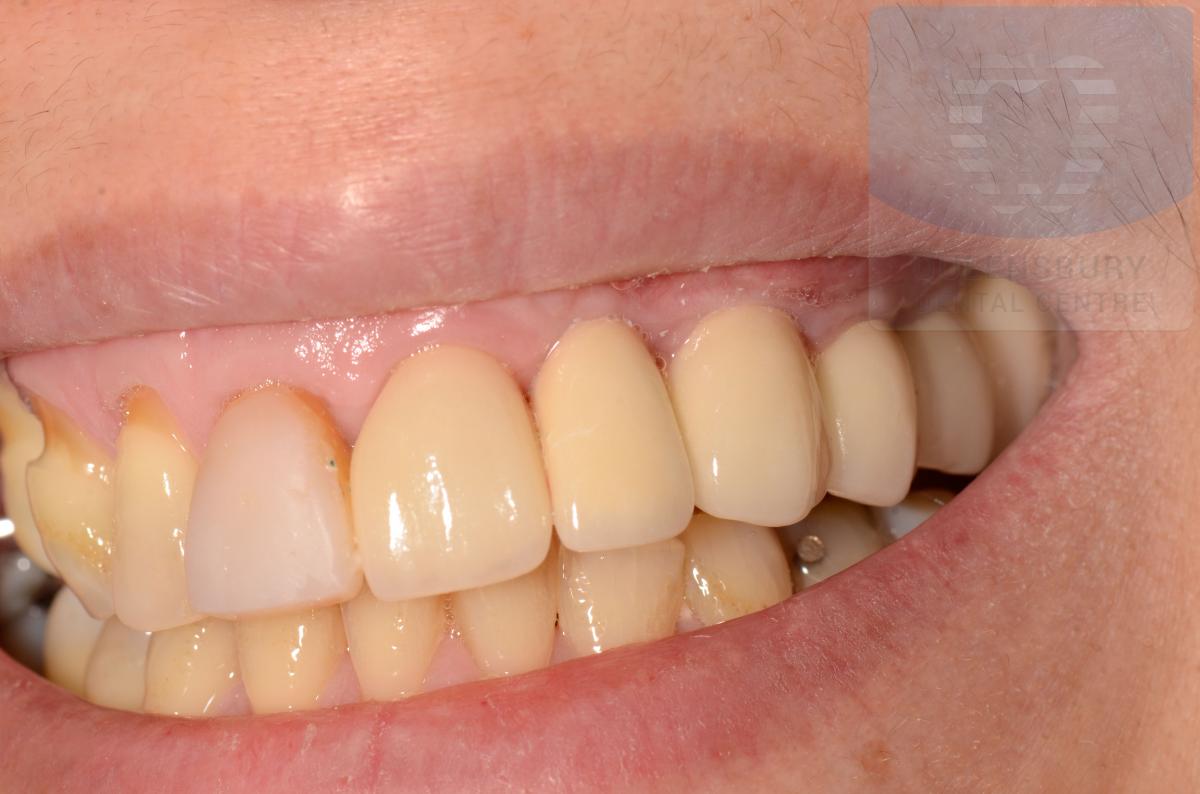

Missing teeth and loose dentures make many people avoid social settings because they are too self-conscious about their appearance. Current dental procedures, however, replace everything from a single missing tooth to a completely missing arch. Ask your dentist or dental specialist about the different dental options that are available to you. Don’t let another day go by without taking this important first step to restoring your confidence and your smile!